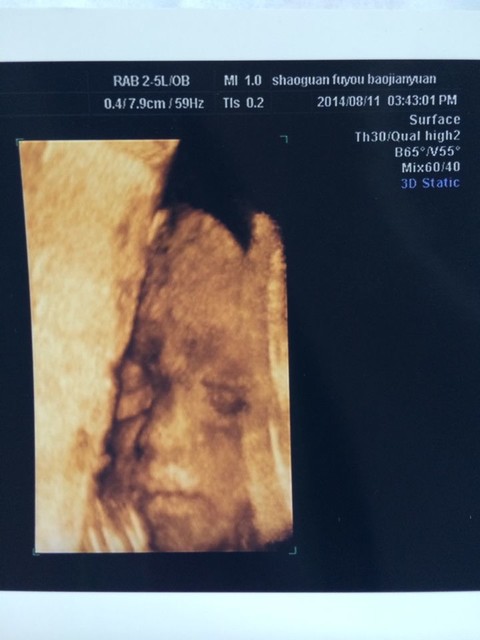

于是,便开始在各大小网站上搜寻所有关于预测生男生女的各种方法。从四维彩超单子看男女,就是如今网传得最“神”、也是关注度最高的方法之一。

有人说四维彩超单上的F和M字母代表胎儿性别,m开头是男孩f是女孩对,难道四维单子有暗示男女吗?如果真的如传言所说,那么问题又来了,四维单子上怎么看m和f呢?

其实,医生根本不可能在四维彩超上面注明是男是女,更不会通过字母代表。这是国家法律规定,请不要瞎想。所谓的M与F只不过是孕期检查时一般的记录缩写罢了。如:

之所以关于四维彩超单上都有F和M预测宝宝性别的方法被广泛流传,那只不过是一些宝妈通过身边亲朋好友的彩超单观察所推断出来的“经验”而已。

要想从彩超中准确无误的看性别,一定要在进去在B超机显示器上看(打印出来的根本看不清楚)。还有 如果那里有实习医生的话他们多多少少都会交流男女宝。说长的很好的一般是男宝,长很漂亮的多半是女宝。